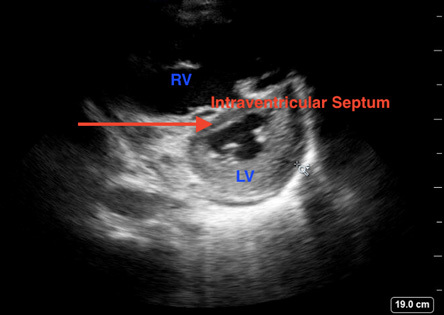

Echocardiography cannot be reliably used to diagnose PE; however, it can be used to assess for right ventricular (RV) dysfunction, which can be indicative of right heart strain from PE in patients with high suspicion.34 Point-of-care ultrasound frequently is used in the ED to evaluate for RV strain. Features such as the abnormal septal motion (D-sign), right ventricular hypokinesis (McConnell’s sign), and increased RV:LV ratio all have very low sensitivity but high specificity for PE in patients with concern for VTE.35 Additionally, a free-floating thrombus may be visualized in the right atrium or ventricle known as a clot-in-transit, which carries a high mortality.36 Evidence of right heart dysfunction or visualized thrombus can be used to guide empiric treatment in patients with high likelihood of PE who are too unstable to undergo additional imaging. (See Figures 2 and 3.)

Figure 3. Septal Bowing Caused by Right Ventricular Strain Demonstrating Classic D Sign |

Point-of-care ultrasound image demonstrating a parasternal short view with septal bowing (red arrow) caused by right ventricular strain demonstrating classic “D sign” |

Image courtesy of Daniel Migliaccio, MD. |